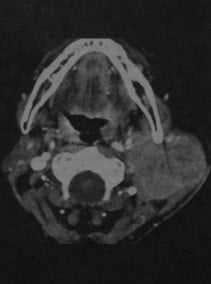

Рак околоушной железы. КТ в горизонтальной плоскости: в левой околоушной железе визуализируется крупное сблидное образование с выраженным усилением.